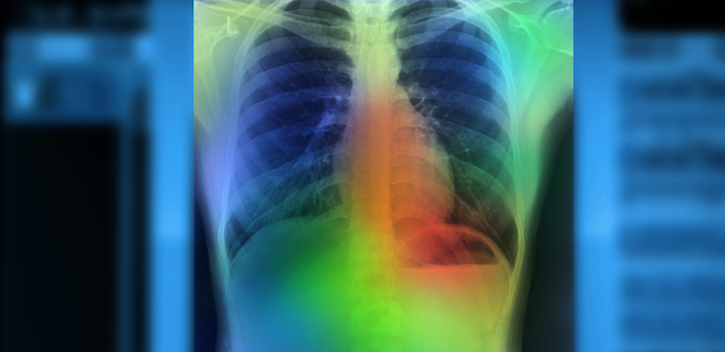

An artificial intelligence (AI) system accurately identified key findings in chest X-rays of patients in the emergency department suspected of having pneumonia in just 10 seconds, researchers from Intermountain Healthcare and Stanford University reported at the European Respiratory Society’s International Congress 2019.

The research team used CheXpert, an automated chest X-ray interpretation model that uses AI, to review images taken at emergency departments at Intermountain hospitals in Utah. The Stanford Machine Learning Group used 188,000 chest imaging studies to create CheXpert, which determines what is and is not pneumonia on an X-ray.

CheXpert outperformed the current system and created the report in less than 10 seconds, compared to 20 minutes to hours with the natural language processing tool.